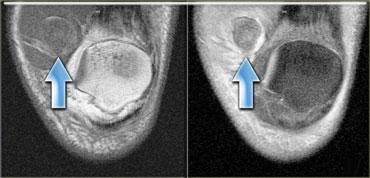

Đây là hình ảnh rách hoàn toàn cơ thẳng đùi (mũi tên).

Cấu trúc giải phẫu có thể rất phức tạp.

Ví dụ, ở phía bên trái là cơ thẳng đùi, có thể biểu hiện nhiều dạng phù nề khác nhau tùy thuộc vào vị trí (giải phẫu) của tổn thương.

Mũi tên màu xanh chỉ gân của đầu gián tiếp, xuất phát từ khớp háng, có hướng thẳng đứng trên hình ảnh cắt ngang này.

Dọc theo phần sau của cơ (mũi tên màu vàng), có một vùng gân dẹt xuất phát từ khớp gối.

Khi một cơ có các gân với hướng khác nhau, điều đó có nghĩa là có thể xuất hiện các dạng phù nề khác nhau tùy thuộc vào gân bị tổn thương.

Do đó, đây là dạng phù nề tương ứng với tổn thương xuất phát từ khớp gối.

Ở ngoài cùng bên trái là hình ảnh rách hoàn toàn đầu gián tiếp của cơ thẳng đùi (mũi tên vàng).

Vết rách này xuất phát từ khớp háng.

Hình ảnh bên cạnh, cũng đã được trình bày ở trên, cho thấy một phát hiện hoàn toàn khác.

Có phù nề bao quanh gân xa kết nối với xương bánh chè.

Gân còn lại hoàn toàn bình thường (mũi tên xanh).